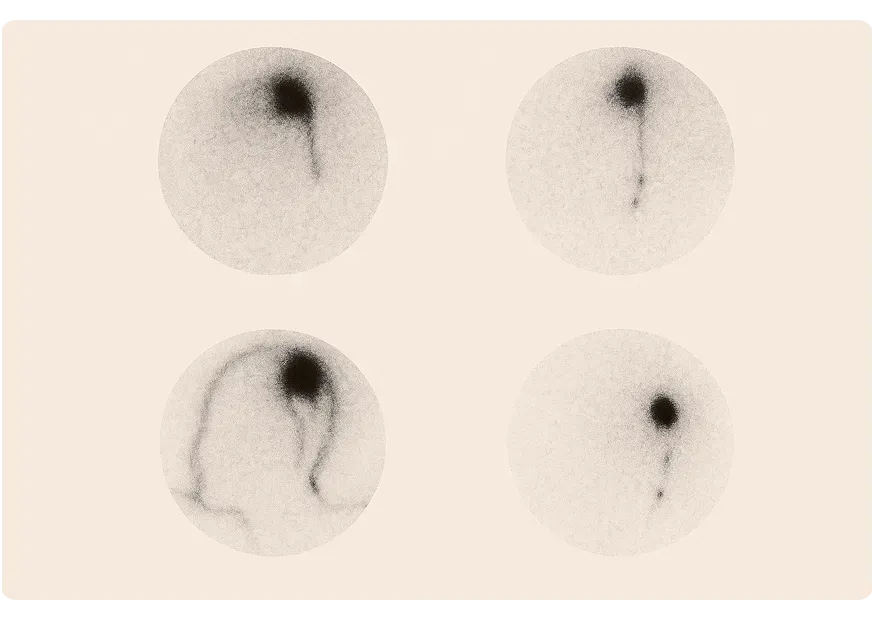

How the Sentinel Node Is Detected

Before surgery, indocianine green, is injected in the uterine cervix. This travel to the lymphatic system, revealing the sentinel node during surgery.

Once identified, the sentinel node is removed and examined by a pathologist. If no cancer is found, there’s no need for full lymph node removal. But if cancer is detected, additional lymphadenectomy may be performed for complete staging.